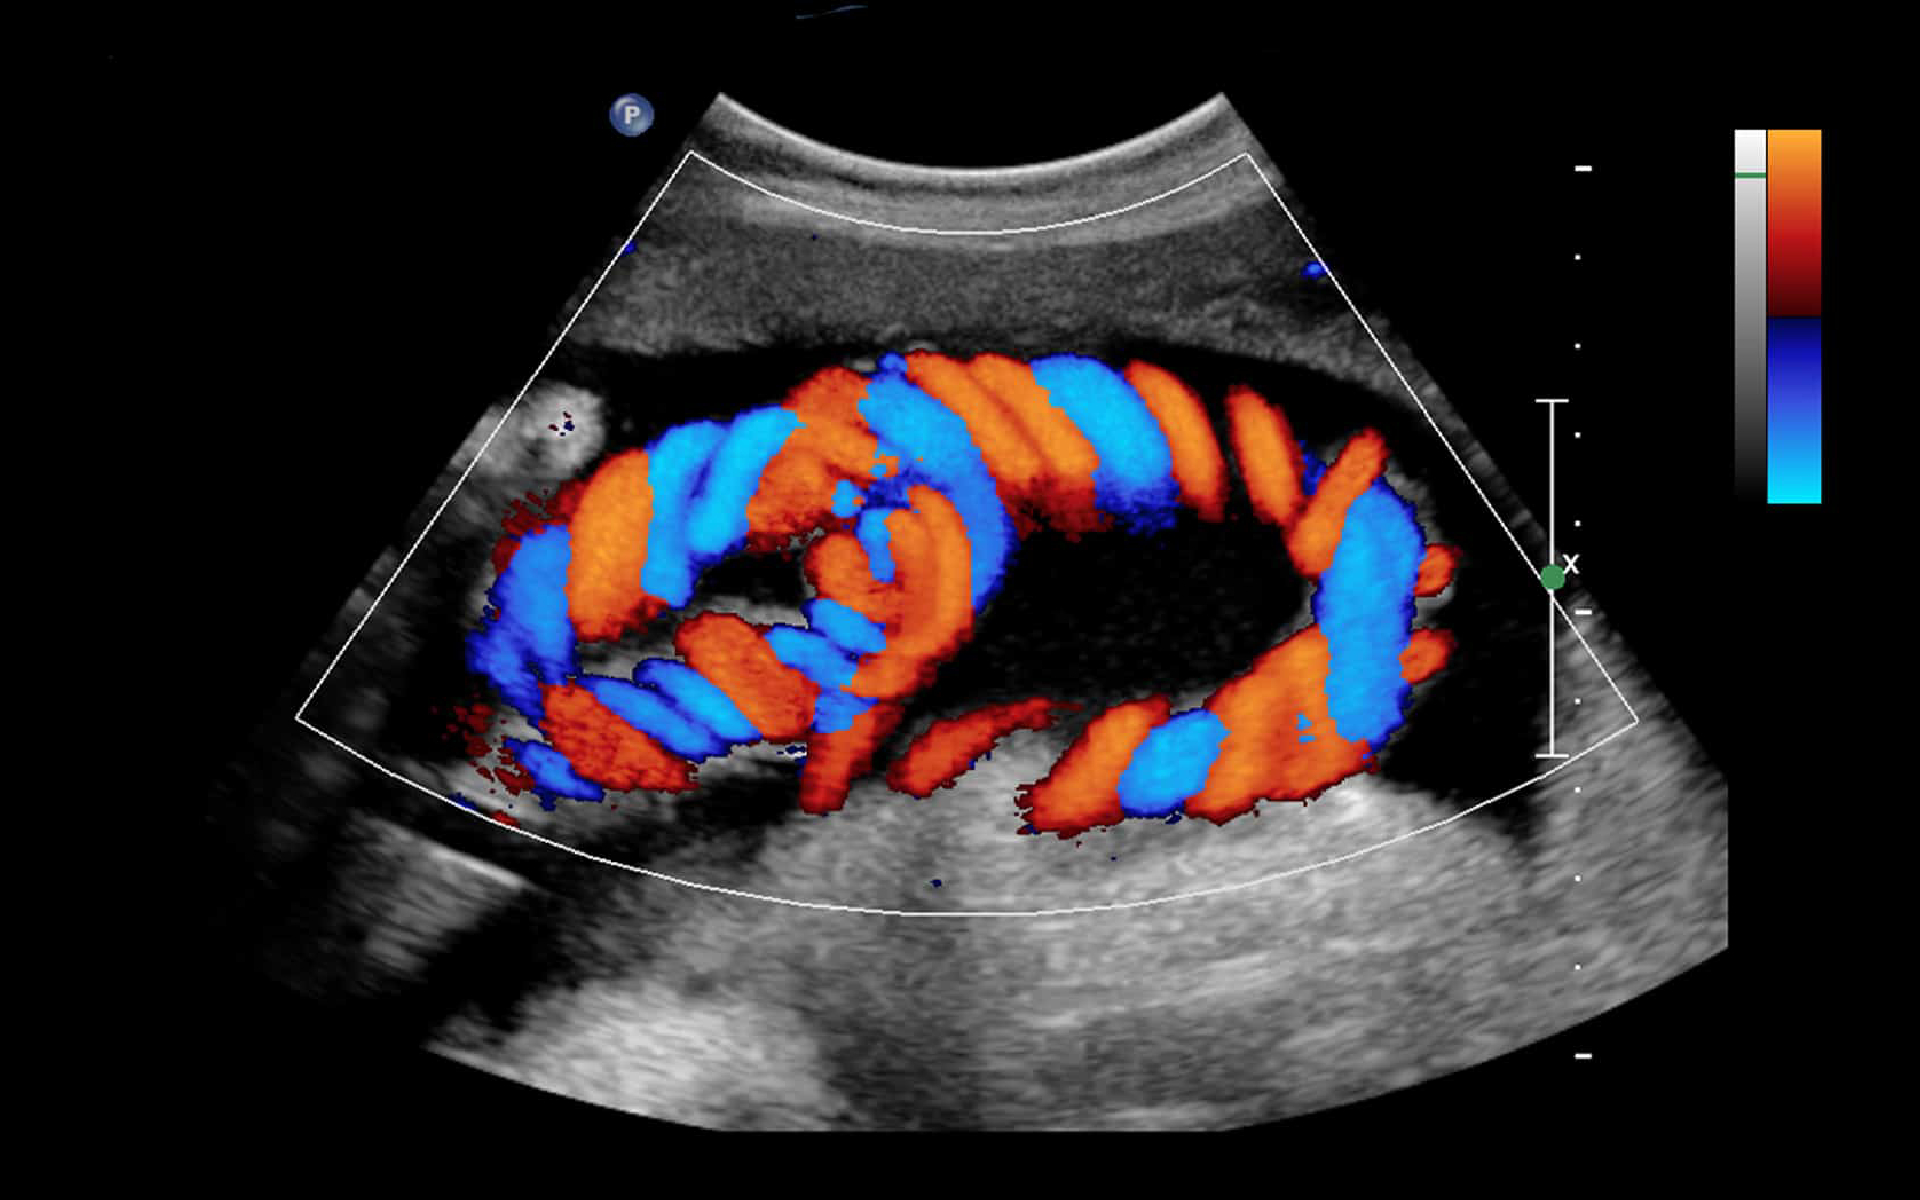

A Colour Doppler Scan is a critical diagnostic tool used to visualize and measure blood flow through your blood vessels. At Liberty Healthcare, we provide the most reliable Colour Doppler scan in Malad and Goregaon, utilizing high-frequency sound waves to provide real-time color-coded images of circulation.

Essential for monitoring high-risk pregnancies and vascular conditions. Get clear, high-resolution imaging at our Malad West center.